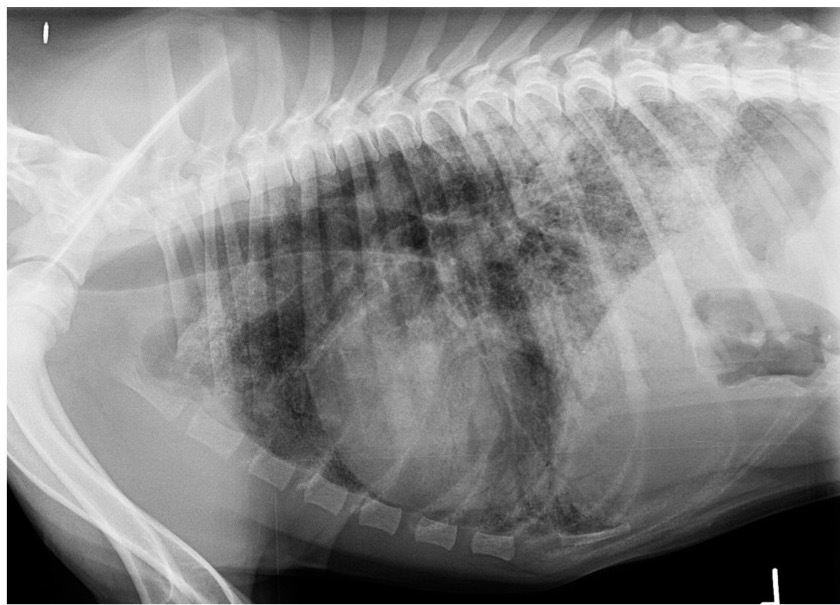

Which lung pattern is shown here?

A

Alveolar

This is limited to the diaphragmatic lung lobes.

There is border obliteration of the diaphragm.